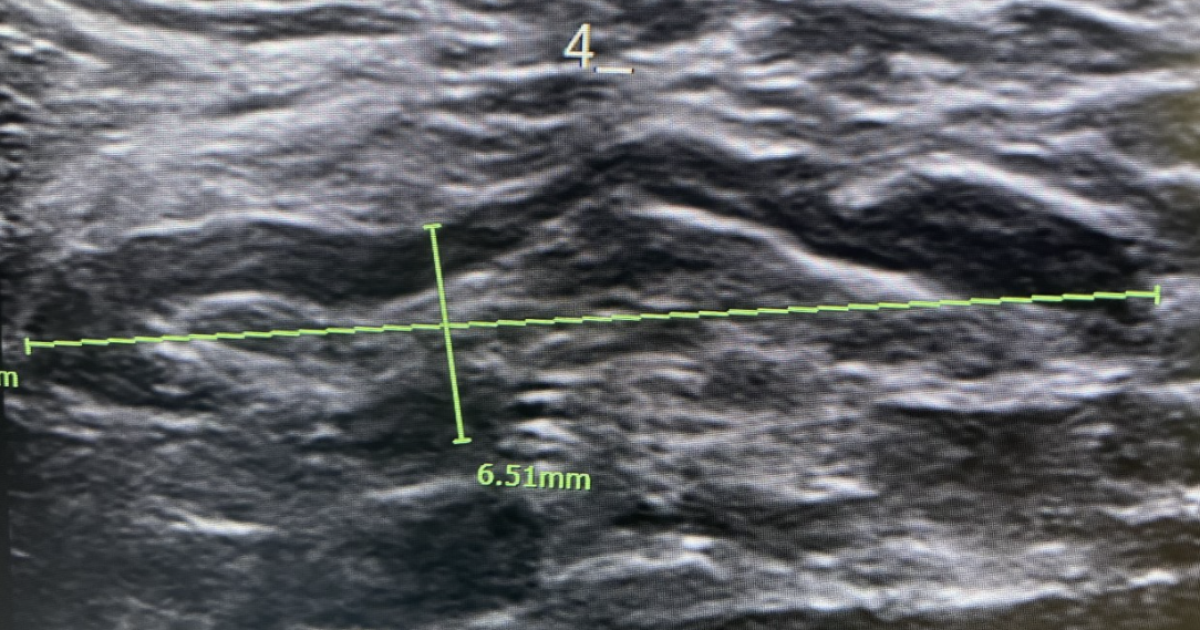

"When we do an ultrasound, there's a typical appearance of lymph nodes that are inflamed or reactive that we see. But yes, it can range in size... just like from the spectrum of getting no lymph nodes, to small, to larger lymph nodes - that can range,” says Dr. Threasa Frouge, Chief Medical Officer of Banner Imaging.